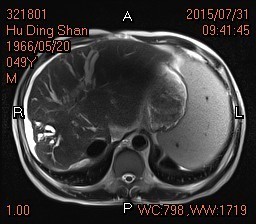

查体:全身皮肤有黄染,见肝掌及蜘蛛痣,腹肌软,腹部可见陈旧性手术疤痕,移动性浊音阴性,肠鸣音正常。 辅查: 腹部MRI:1.肝硬化,脾大,少量腹水,食道下段、胃底及脾门周围静脉曲张。 2.肝内胆管、左肝管扩张,门脉淋巴水肿;腹膜后、心膈角区多发肿大淋巴结,请结合临床。 3.胆囊术后缺如。 4.胰腺体尾部未见显示。